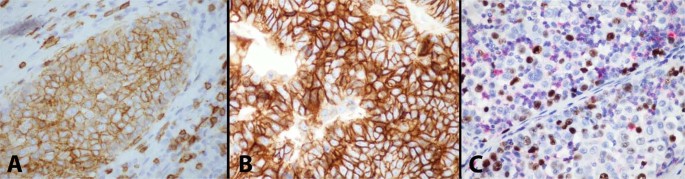

Representative material was available for immunohistochemical studies in 92 cases. All cases in the study showed strong nuclear positivity of the tumor cells for p40 and p63, and strong cytoplasmic staining for cytokeratin AE1/AE3. In 60/92 cases (65%), PAX8 showed diffuse nuclear staining in most of the tumor cells like that seen for p40/p63. 12/92 (13%) cases showed only weak, patchy and focal positivity for PAX8 in scattered cells. EMA was focally positive in 18/92 (20%) cases but only in the small areas of abrupt keratinization; in 3 cases, however, EMA also stained the sheets of polygonal tumor cells unassociated with the foci of abrupt keratinization. Chromogranin and synaptophysin were convincingly positive in only one case. Calretinin was negative in all cases. The lymphoid cell component strongly labeled with CD3, TdT and bcl-2 in all cases. CD20 showed a few scattered positive lymphocytes around dilated perivascular spaces and was also strongly positive in the lymphocytes in the stroma and lymphoid follicles of the cases that harbored a micronodular thymoma component. Bcl-2 also showed cytoplasmic staining of the epithelial tumor cells in 22/32 (69%) cases of atypical thymoma with spindle cell features and in the spindle cell component in 6/12 (50%) cases of mixed squamoid/spindle cell atypical thymoma. CD5 was positive in the epithelial tumor cells in 23/92 cases (25%); the staining pattern was diffuse membranous, or cytoplasmic and membranous (Fig. 6A). CD117 was positive in the epithelial tumor cells in 13/92 cases (14%); the staining pattern was mainly membranous and diffuse (Fig. 6B). CD117 was also positive in the thymic carcinoma component in 14/16 (88%) cases. Distribution of the staining patterns for CD5 and CD117 in our cases is shown in Table 2. MIB-1 was assessed using a cocktail of MIB-1/CD45 to distinguish the epithelial cells from lymphocytes (Fig. 6C). Overall percentage of MIB-1 positivity in the entire cohort was 11.6%. Table 2 also shows the distribution of the percentages of positivity for MIB1 by histologic type, staging and outcome. The spindle cell type of atypical thymoma showed a slightly higher percentage of nuclear positivity than the squamoid type (13.66% vs. 11.85%). There was also a minimal trend for slightly higher proliferative activity found in higher stages (III–IV) than in the lower stages (I–II). Patients with recurrences and metastases, and those who died of tumor also showed a trend for an increase in the proliferation rate (14.25%, 15.94%, and 16.43%, respectively), but the differences from the mean were minimal. It should be noted, however, that there was wide variability in proliferative activity ranging from 0 to 50% nuclear positivity; however, cases with very low or very high proliferative activity were in the minority and >80% of cases were in the range of 8–20%.

A Immunohistochemical staining for CD5 in atypical thymoma shows strong membrane positivity; notice positive staining in scattered small T-lymphocytes in the stroma; B Immunohistochemical staining for CD117 shows strong membrane staining for this antigen in the tumor cells; C Multiplex staining for Ki-67 and CD45 in atypical thymoma shows increased proliferation rate with ~15% positive nuclei (brown chromogen); notice scattered small lymphocytes (red chromogen) in the background.